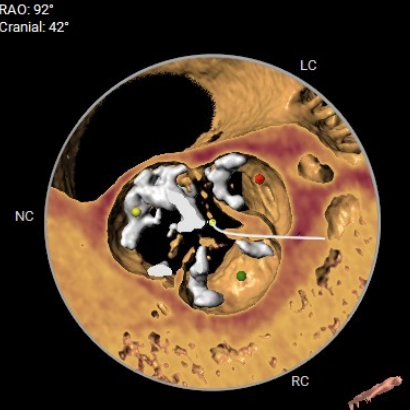

法氏窦三窦直径

左冠状窦:31.5mm;右冠状窦:29.2mm;无窦:33.9mm

主动脉瓣钙化分布(钙化积分:950mm3)

左冠开口高度:

11mm

右冠开口高度:

16.2mm

● 主动脉根部:患者主动脉瓣为三叶瓣,左右冠窦可见部分粘连,重度钙化,瓣环到LVOT层面可见钙化,法式窦结构较大,左冠开口高度约11.0mm,右冠开口高度约16.2mm,STJ高度约19.5mm,直径约28.1mm,升主动脉未见明显扩张,心脏角度约49°,左室形态稍小,心肌增厚。

● 冠脉开口:左冠开口高度低,瓣叶长度可,窦宽相对瓣膜可;右冠开口高度可,瓣叶长度可,窦宽相对瓣膜可。冠脉风险低,建议球扩以进一步评估。